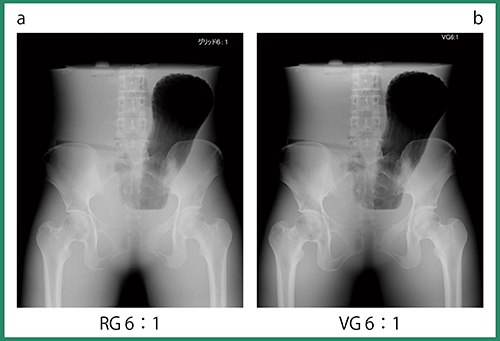

最初に,腹部ファントムを用いて,リアルグリッド(RG)とVirtual Grid(VG)で撮影し画像を比較した(図1)。その結果,VGでは骨盤部の厚みのある部分の骨構造がより明瞭で,また,腸管内のガスも良好に観察可能であった。さらに,VGにて撮影距離120cm,管電圧74kVに設定し,1.4mAsから7.2mAsまでmAs値を変えて撮影したところ,撮影線量を下げても画質は担保されており,線量の大幅な低減が可能と考えられた。

図1 腹部ファントムにおけるRG 6:1とVG 6:1の比較